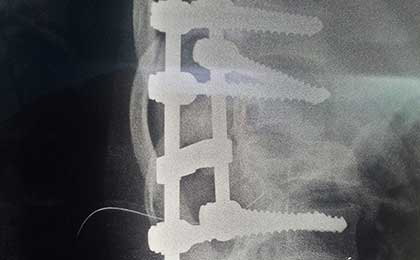

post op x ray lat 1

Spine Fixation Lumbar Spine

• Spine Fixation Lumbar Spine

post op L5 S1 FIXATION